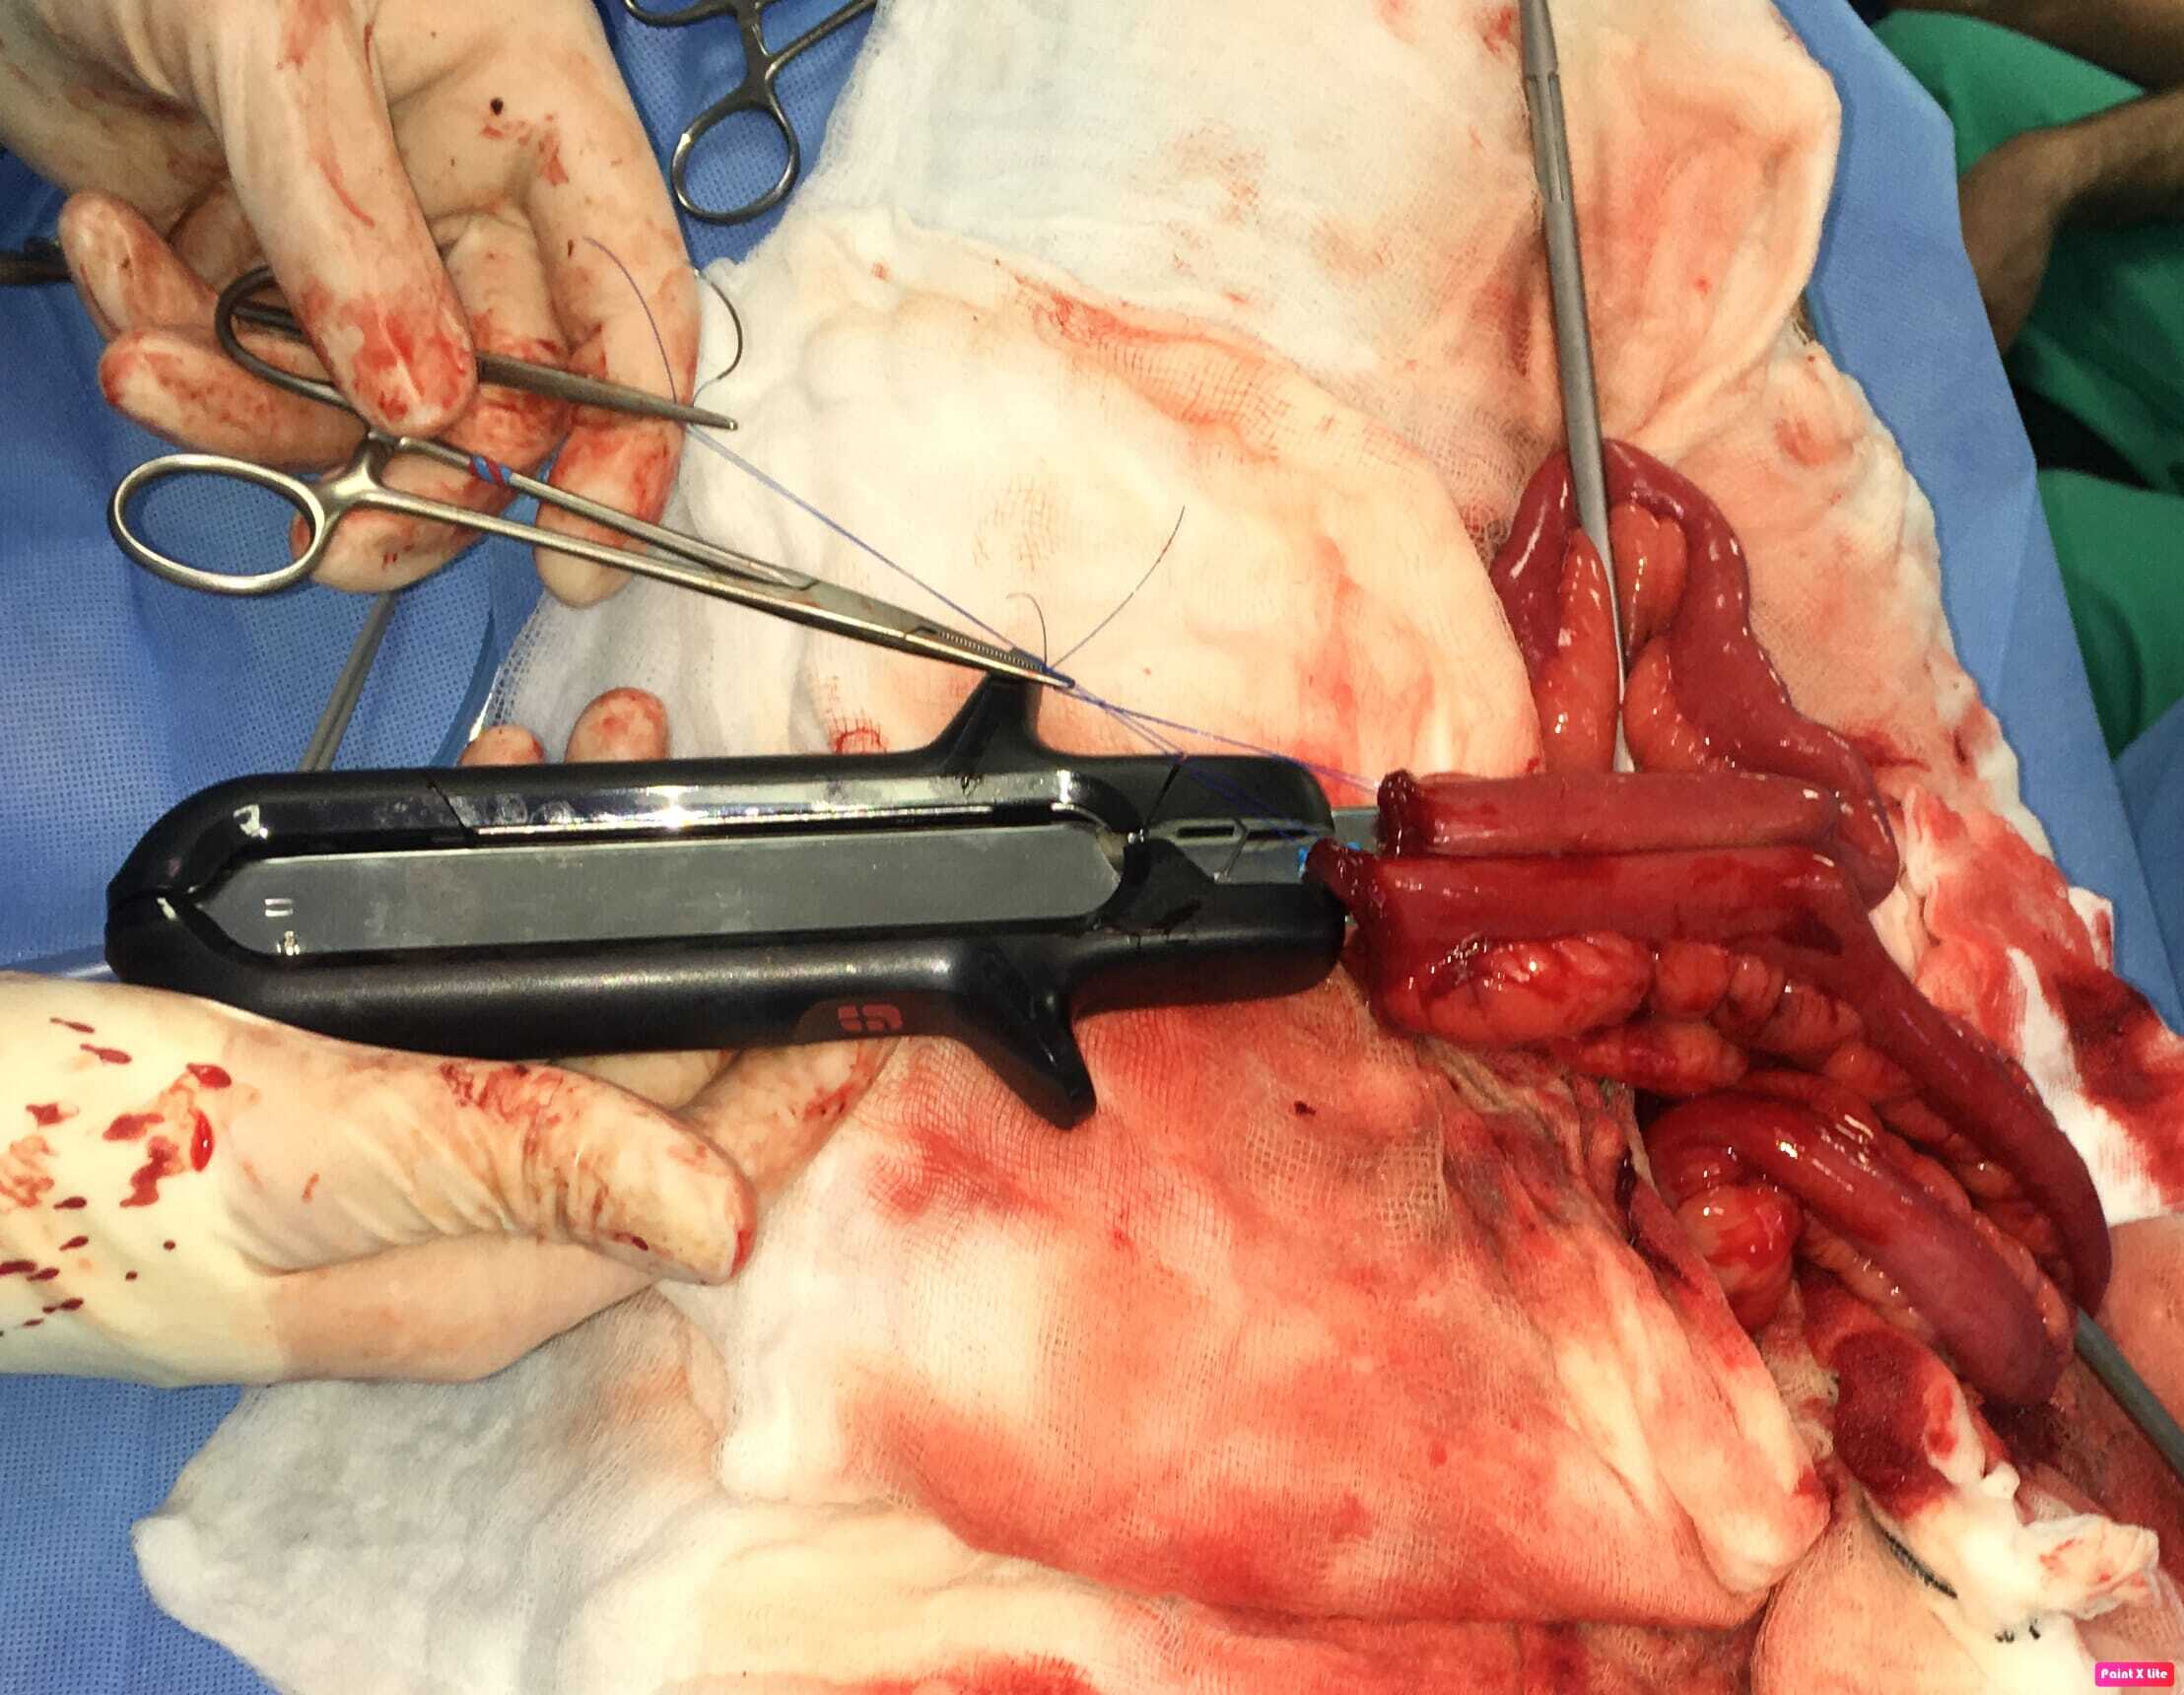

Intraluminal or extraluminal occlusion of the gastrointestinal tract is most often the result of neoplasia or foreign material. Oesophageal foreign bodies are best removed via endoscopy or fluoroscopy (approximately a 90 percent success rate). If they can be advanced into the stomach then surgical retrieval via gastrotomy rather than thoracotomy is less complex. Stay sutures are invaluable when performing gastrotomy to minimise the risk of spilling contents into the abdomen. Tissue viability of the intestines is typically assessed visually and by palpation (an experienced surgeon's assessment is 85 percent accurate), including identification of vessel pulses (thrombosed vessels are dark and do not blanch when compressed) and whether gut bleeds when incised. Sutured anastomosis following enterectomy is the most commonly performed method, using full-thickness single-layer simple interrupted or simple continuous suture patterns. The latter is preferable, as it is simpler, uses less material, is quicker and is more leak resistant. Surgical stapling devices can be used to create functional end-to-end anastomoses ( Box 1). Practitioners may be reluctant to use these devices based on lack of familiarity and cost but there are numerous advantages over traditional suturing, including considerably shorter surgical/anaesthesia time and a reduced risk of dehiscence in a septic abdomen. Overall, these reduce morbidity and cost. Box (1) Step-by-step guide to creating a functional end-to-end anastomosis using a linear stapling device and linear-cutter stapling device